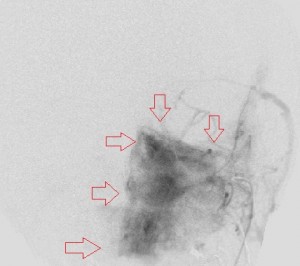

Fourth panel, left to right: Digital subtraction angiogram of the left internal maxillary artery before (1st two images, a frontal and a lateral view of the face) and after embolization (the last image, a lateral view). (For the 2nd and 3rd images, assume the patient’s face is turned to your right). Note the intense blushing of the tumor before embolization emphasizing its vascularity. Following embolization the mass is invisible.